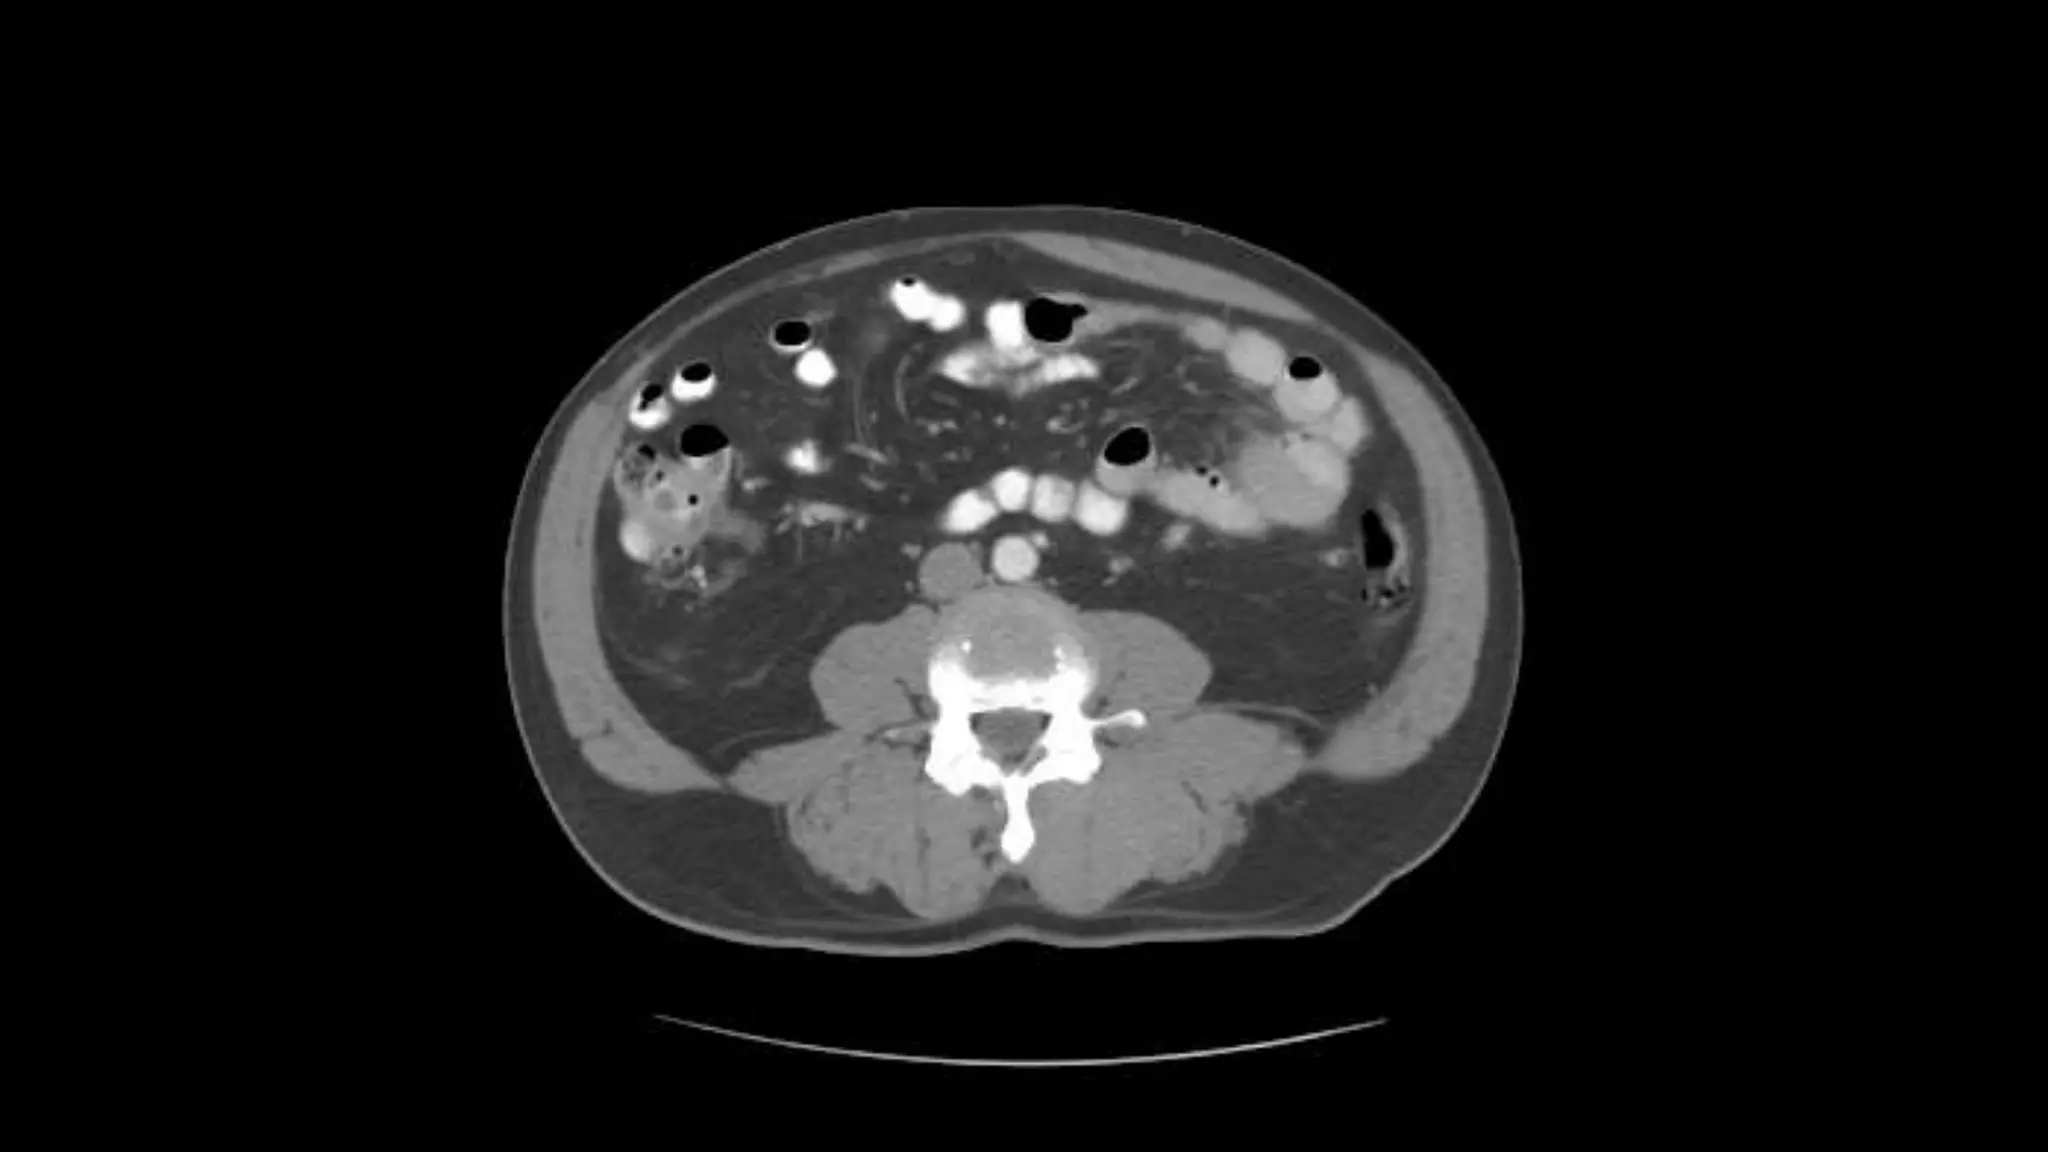

Renal Veins emptying into the IVC. We also see the right renal artery branching

off the Aorta, follow it down till you see it enter the right kidney. The Superior

Mesenteric Vein is outlined on the top of this image. If you follow the SMV up, you

will see it empty into the Portal Vein.

Superior Mesenteric Vein – follow it up as it joins the Splenic

Vein to form the Portal Vein

Transverse Colon Small Bowell

Note inferior mesenteric artery emerging from aorta

Inferior mesenteric vein extends cephalad to join smv.